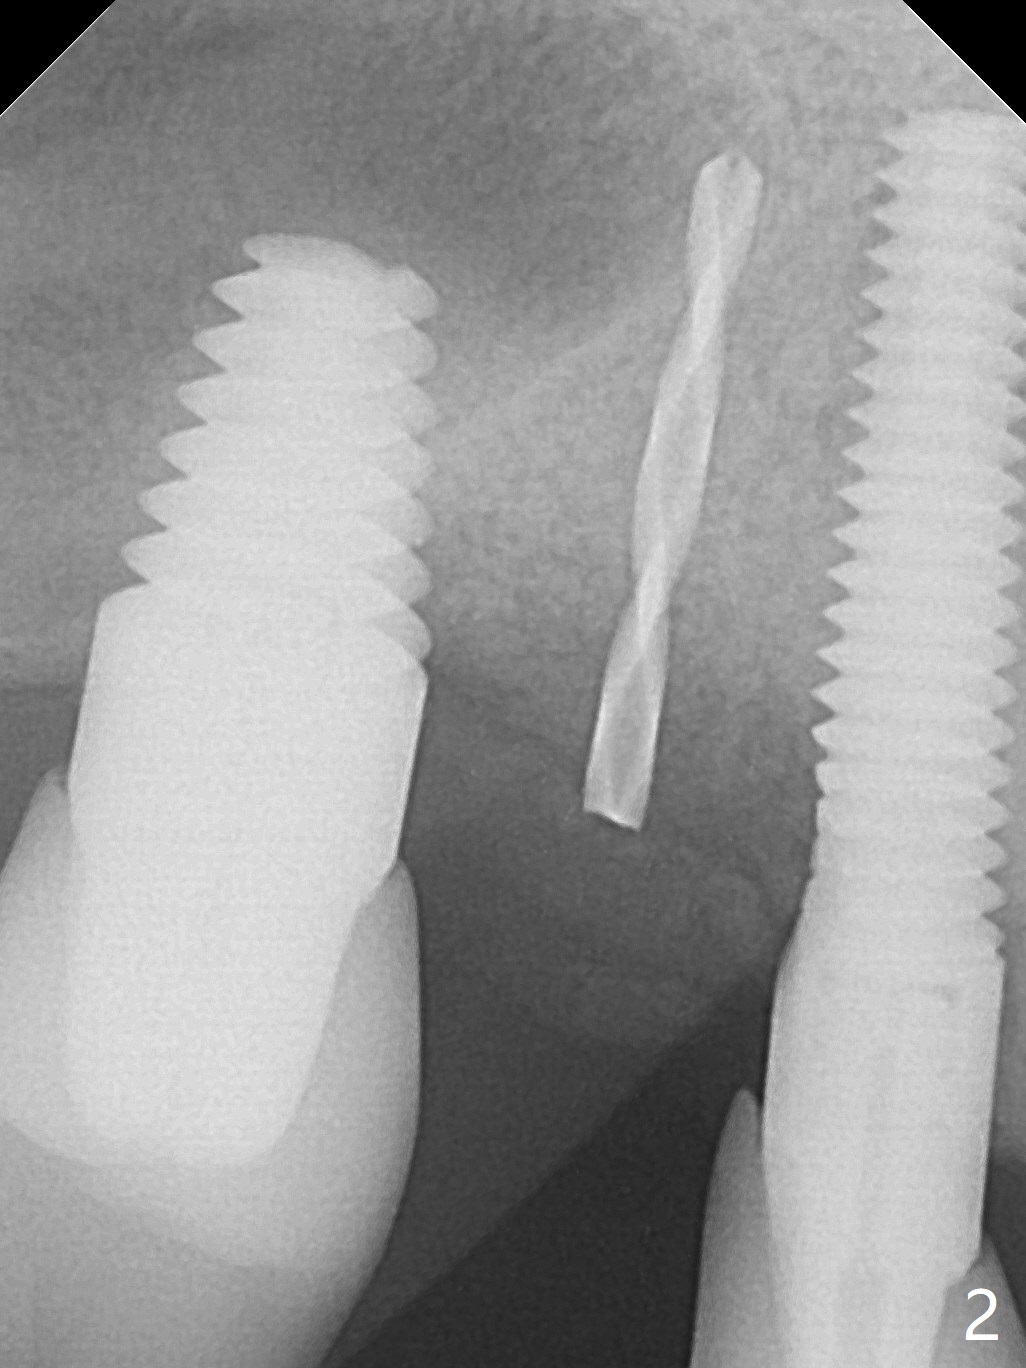

The osteotomy gap at #4 disappears 3.5 months post implant removal with bone graft; the mesiodistal space is 6.6 mm (Fig.1). Incision confirms disappearance of the osteotomy gap. A new osteotomy is established for 10 mm (Fig.2). A 2.5x10(4) mm 1-piece implant is placed with <50 Ncm; since the trimmed implant threads at #5 are exposed (Fig.3), Vanilla graft with Osteogen is placed mesial and distal to the new small implant (Fig.4 *). There is no bone loss 3.5 months postop (Fig.5,6). After cementation of the crown (Fig.7 C) with the thin abutment (*), the patient feels that the crown has mobility. The crown in fact has no clinical mobility; it cannot be removed. After occlusal equilibrium, the patient does not feel the same. The thin 1-piece implant must flex under heavy occlusion. The patient is a bruxer. There is no crestal bone resorption 4 months post cementation (8 months post cementation, Fig.8,9). There is no sign of periimplantitis anymore. The implant remains mobile and symptomatic (chewing pain) 14 months post cementation (Fig.10). There is no bone loss 2 years 4 months post cementation (Fig.11).